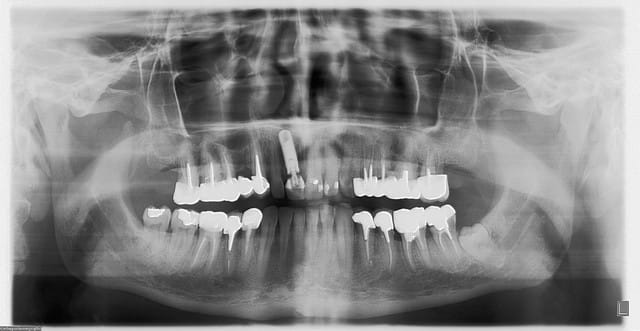

bon, c'est fait...extrac/implantation immédiate/ prov immédiate...merci pour vos tutos...;-)) çà m'a bien aidé...

implant Zimmer 4.7/16, membrane vestibulaire Zimmer socket repair, comblement au biooss...

pilier qui traverse la membrane...

juste surpris que le pilier prov en plastique soit pas radio-opaque...

j'ai volontairement un peu angulé vers la 12 car le canal palatin étais volumineux (vu au scan) et je voulais pas taper dedans...(maintenant la déformation géométrique de la pano amplifie un peu le phénomène...)